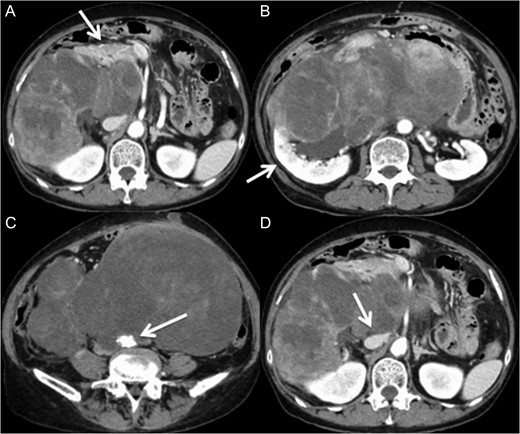

A 60-year-old female visited a clinic because of abdominal distension. She noticed abdominal distention one year prior to her clinical visit, but she left it for a year. Gradual enlargement of the mass eventually made her decide to see a doctor. Enhanced abdominal computed tomography (CT) revealed large retroperitoneal tumors. Mini-laparotomy and tumor biopsy confirmed her diagnosis as dedifferentiated liposarcoma, then she was referred to us for further examination and treatment. A multidetector CT scan revealed a hypodense mass in the retroperitoneum, with a size of ~30 × 20 cm2. The tumor appeared to invade the duodenum, head of the pancreas, right kidney, IVC and abdominal aorta (Fig. 1). The IVC was almost occluded by the tumor, but venous return from the lower extremities beyond the tumor was observed through collateral veins around the tumor (Fig. 2). The tumor invaded the abdominal aorta just below the left renal artery to the common iliac artery bifurcation, although the root and entire length of SMA appeared to be free from the tumor (Fig. 3). She underwent en bloc resection of the RL with resection of the right kidney, duodenum, head of the pancreas, a portion of the inferior IVC and abdominal aorta. Ax-F & F-F bypass was performed for vascular reconstruction using poly-tertrafluoroethylene (PTFE) to maintain the blood flow to the both lower extremities (Fig. 4). The lower abdominal aorta and both sides of common iliac arteries were resected with the tumor. The proximal stump of the abdominal aorta was closed with a running suture and covered by the omentum. The IVC was resected from just below the left renal vein to the common iliac veins. Reconstruction of the venous system including IVC and common iliac veins was not performed because venous collateral pathways had already developed sufficiently. Child’s reconstruction was performed after pylorus-preserving pancreatoduodenectomy. The duration of the surgery was 19 h 22 min, and blood loss was 4 811 mL, requiring 1680 mL of red blood cell transfusion. The tumor was 33 × 20 × 13 cm3 in size, weighed 4800 g, and had a fibrous capsule (Figs 5 and 6). Pathological examination revealed a dedifferentiated liposarcoma with negative margin (Fig. 7). Tumor invaded the pancreatic capsule, the renal capsule, the adventitia of the IVC and the abdominal aorta and infiltrated into the muscularis propria and focally into lamina propria of the duodenum. Edema of the both lower extremities was noted as postoperative complication, but that was gradually resolved by diuretics. The patient was discharged 37 days after surgery without serious postoperative complications such as pancreatic fistula, as well as graft infection or obstruction of two bypasses. Currently, she remains alive and well with no evidence of recurrence at 16 months post-operation.

Multidetector CT scan (axial view). The large retroperitoneal tumor was adjacent to the duodenum, the head of the pancreas (A) and the right kidney (B). The tumor surrounded the abdominal aorta (C) and the inferior vena cava (D).